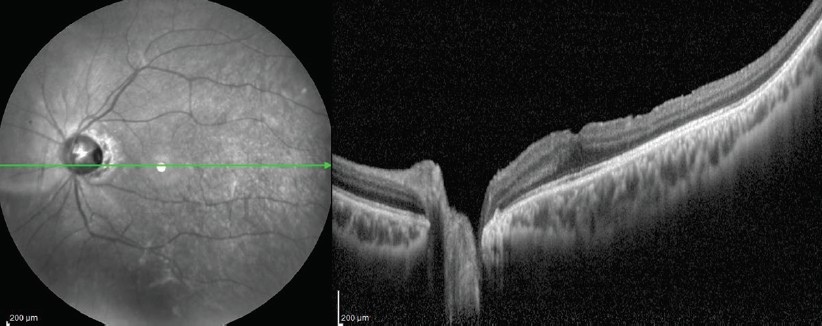

<p>Figure 4. OCT imaging in ODP can reveal connections between the subretinal and intraretinal space, the perineural space, and the vitreous cavity.</p>

Figure 4. OCT imaging in ODP can reveal connections between the subretinal and intraretinal space, the perineural space, and the vitreous cavity.

We have applied this technique to five patients in the past 5 years when pneumatic displacement did not resolve the pathology. Reabsorption of subretinal fluid might take a few months, even in cases in which the ILM flap is visible in the pit on postoperative OCT (Figure 5).

<p>Figure 5. OCT of the left eye of the patient depicted in Figure 2. The horizontal scan of the OCT (A) shows the depth of the coloboma. Identification of the fovea can be challenging in cases of ODP and is not possible in this particular case because it is located inside the coloboma. A mild amount of subretinal fluid is visible. The color photo (B) shows the extensive coloboma and the level of the OCT scan in the extramacular temporal areas shown below.</p>

Figure 5. OCT of the left eye of the patient depicted in Figure 2. The horizontal scan of the OCT (A) shows the depth of the coloboma. Identification of the fovea can be challenging in cases of ODP and is not possible in this particular case because it is located inside the coloboma. A mild amount of subretinal fluid is visible. The color photo (B) shows the extensive coloboma and the level of the OCT scan in the extramacular temporal areas shown below.